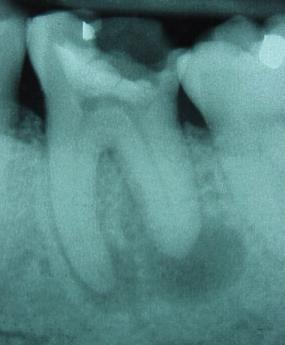

![]() |

és gyökértömés után. Már csak a fedőtömés hiányzik. |